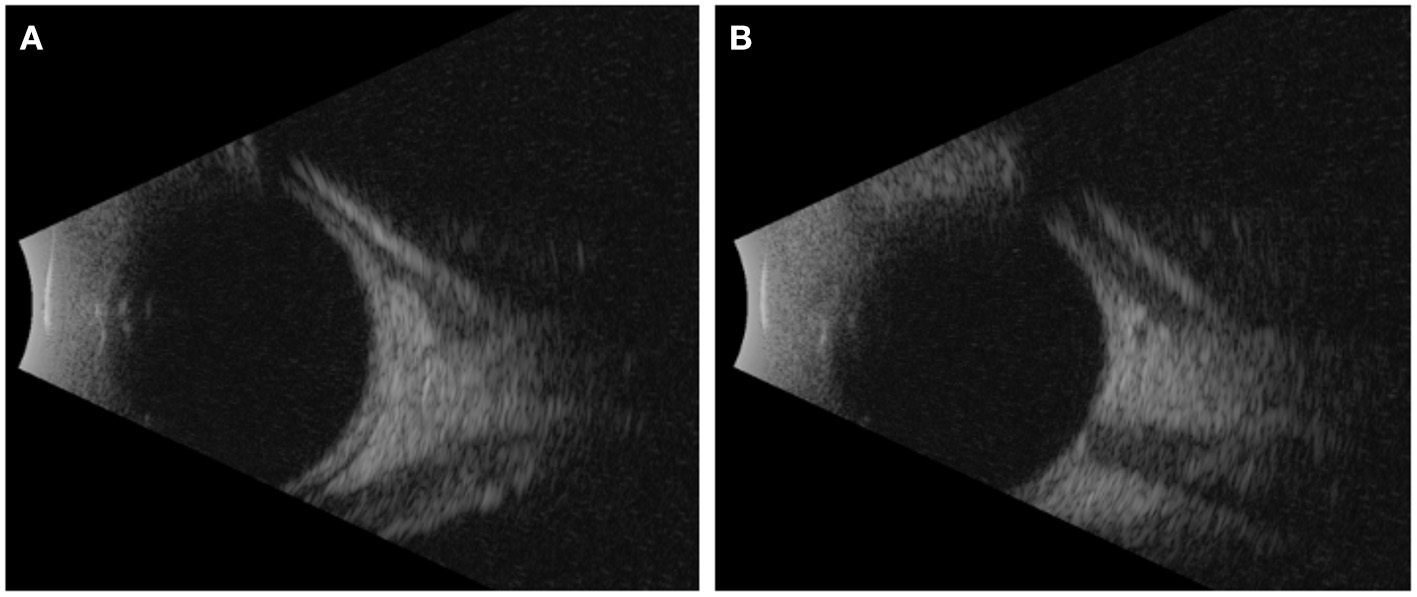

On exam and diagnostic imaging with B-scan ultrasound, there was no rubeosis, and no choroidal or retinal detachments were noted (Figure 2). Clinical examination and ultrasound biomicroscopy (UBM) revealed significant anterior chamber shallowing without pupillary block or synechiae, which improved significantly with topical cycloplegia with cyclopentolate 0.5% (Figure 3). With oral acetazolamide and topical IOP-lowering eyedrops, her pressures improved but were still elevated to the 30- to 35-mmHg range, and the corneal clouding still prevented adequate gonioscopic visualization of angle anatomy. Fundus examination revealed persistent stage 3 ROP with inadequate laser, particularly nasally; however, the view was still somewhat limited for additional laser photocoagulation (Figure 1). She underwent intravitreal injection of bevacizumab 0.625 mg in both eyes at 39 weeks of PMA. In both eyes, regression of ROP after laser and intravitreal bevacizumab was noted by 41 weeks of PMA (2 weeks after injections). Despite moderate improvement in the anterior chamber depth (Figure 3) and IOP, medical treatments were ultimately determined to be inadequate, and the patient required ab externo trabeculotomy in the right eye at 42 weeks of PMA and left eye at 44 weeks of PMA. With parental consent, genetic screening for congenital glaucoma through the Prevention Genetics Glaucoma Panel was obtained and found to be negative.

A 450-g female infant was born at 24 weeks and 5 days of gestational age by normal spontaneous vaginal delivery at an outside hospital and transferred to our institution at a postmenstrual age (PMA) of 33 weeks and 2 days for patent ductus arteriosus ligation. At our institution, she underwent an initial ROP screening, which showed stage 0 immature vessels in zone 2 of both eyes. There were clear views of the fundus in both eyes. The patient was then transferred back to the home referring hospital where she underwent two sessions of diode laser in both eyes at 36 and 37 weeks of PMA for treatment-requiring ROP. Due to concern for inadequate laser and poor fundus view with corneal haze, she was re-referred to our institution. Upon reevaluation, she was noted to have cloudy corneas, intraocular pressure (IOP) of 40–45 mmHg, and persistent zone 2, stage 3 ROP, with peripheral laser scars in both eyes (Figure 1).